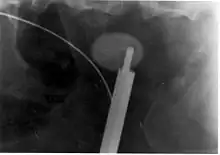

Where a CT scan is unavailable, an intravenous pyelogram may be performed to help confirm the diagnosis of urolithiasis. This involves intravenous injection of a contrast agent followed by a KUB film. Uroliths present in the kidneys, ureters, or bladder may be better defined by the use of this contrast agent. Stones can also be detected by a retrograde pyelogram, where a similar contrast agent is injected directly into the distal ostium of the ureter (where the ureter terminates as it enters the bladder).[61]